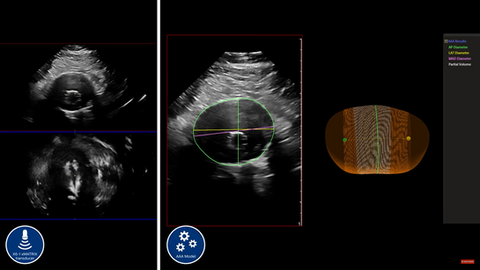

Já o moderno transdutor Philips X6-1 emerge como uma ferramenta de relevância no âmbito do ultrassom vascular abdominal.

A capacidade de capturar imagens com a tecnologia x-plane permite a visualização simultânea nos planos longitudinal e transversal em tempo real, viabilizando a mensuração volumétrica dos vasos. Essas aquisições são particularmente cruciais no acompanhamento dos aneurismas de aorta e avaliações das endopróteses implantadas.